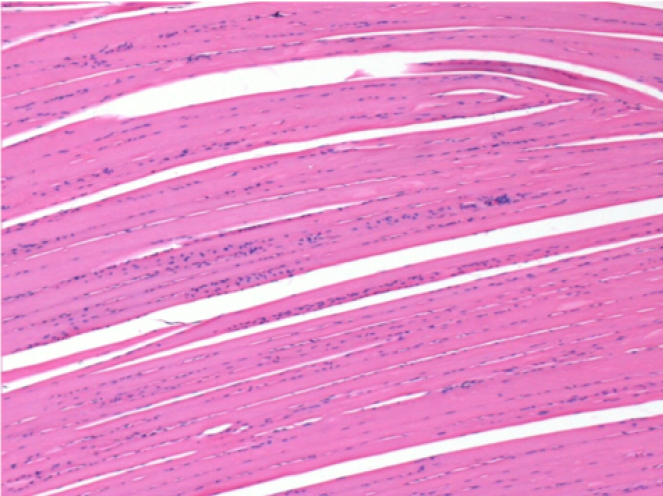

7 months (D210)after Endopeel IM Injection 0.1ml in the right pretibial muscle.

Complete Restitutio ad integrum after 7 months